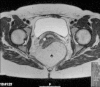

Presentation of case: We describe a case of a 44 year old patient with a laparoscopic approach for the removal of a retrorectal tumor and emphasize on the preoperative diagnostics and the intraoperative, minimal invasive approach.

Discussion: Especially because these tumors are rare and often an incidental finding in gynecologic surgery, it is important to know the various differential diagnoses and its consequences with the laparoscopic approach.

Conclusion: We suggest the laparoscopic approach in cases of retroperitoneal cysts of unknown origin is ideal also because anatomic structures, mostly nerves, can be easily spared.